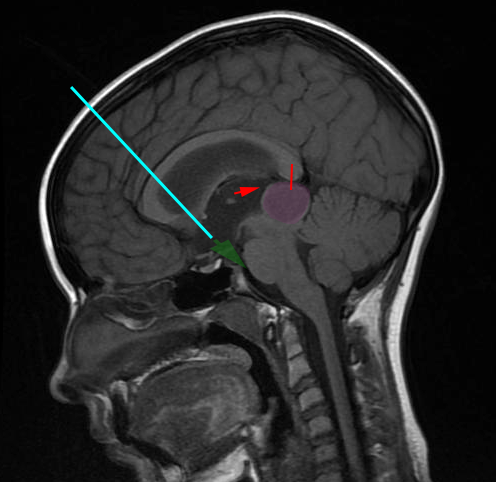

Η επέμβαση γίνεται με τον ασθενή υπό γενική αναισθησία. Η προσπέλαση στο κοιλιακό σύστημα του εγκεφάλου γίνεται μέσω μικρής κρανιοτομίας, συνήθως δεξιά μετωπιαία, και με την βοήθεια ενδοσκοπίου. Η οπή από την οποία παροχετεύεται το Ε.Ν.Υ. γίνεται στο έδαφος της τρίτης κοιλίας του εγκεφάλου με την βοήθεια ειδικού καθετήρα.

Η ενδοσκοπική τρίτη κοιλιοστομία δεν είναι κατάλληλη για ορισμένους ασθενείς των οποίων οι ανατομικές συνθήκες του εγκεφάλου δεν επιτρέπουν ασφαλή προσπέλαση στην 3η κοιλία ή στην προγεφυρική δεξαμενή του εγκεφάλου, όπου θα πραγματοποιηθεί η παροχέτευση του Ε.Ν.Υ. Αυτό πρέπει να αποτελέσει αντικείμενο προεγχειρητικού σχεδιασμού και αξιολόγησης και να κατευθύνει την επιλογή των ασθενών. Επίσης ασθενείς με όγκο εγκεφάλου, παλαιότερη βαλβίδα, υπαραχνοειδή αιμορραγία και αυτοί που έχουν πραγματοποιήσει ακτινοθεραπεία εγκεφάλου έχουν χειρότερη έκβαση. Οι επιπλοκές δεν είναι συχνές και περιλαμβάνουν τραυματισμό του υποθαλάμου, παροδικές παρέσεις οφθαλμοκινητικών συζυγιών και αιμορραγία.